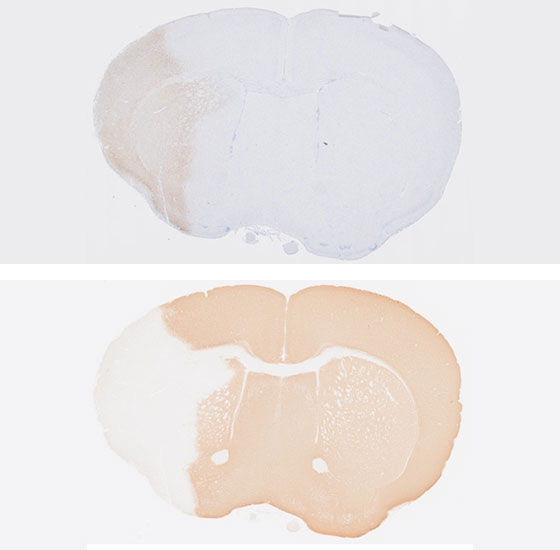

本研究領域では、炎症が収束する際の生体反応を、組織レジリエンス、炎症記憶として研究を進める一方で、慢性炎症時の病態形成機構について、「炎症性組織レジリエンス」、「病的炎症記憶」および「組織障害エントロピー」として捉え、複数の生体システムの連関の観点から研究を推進することにより新たな炎症収束学の創成を目指します。